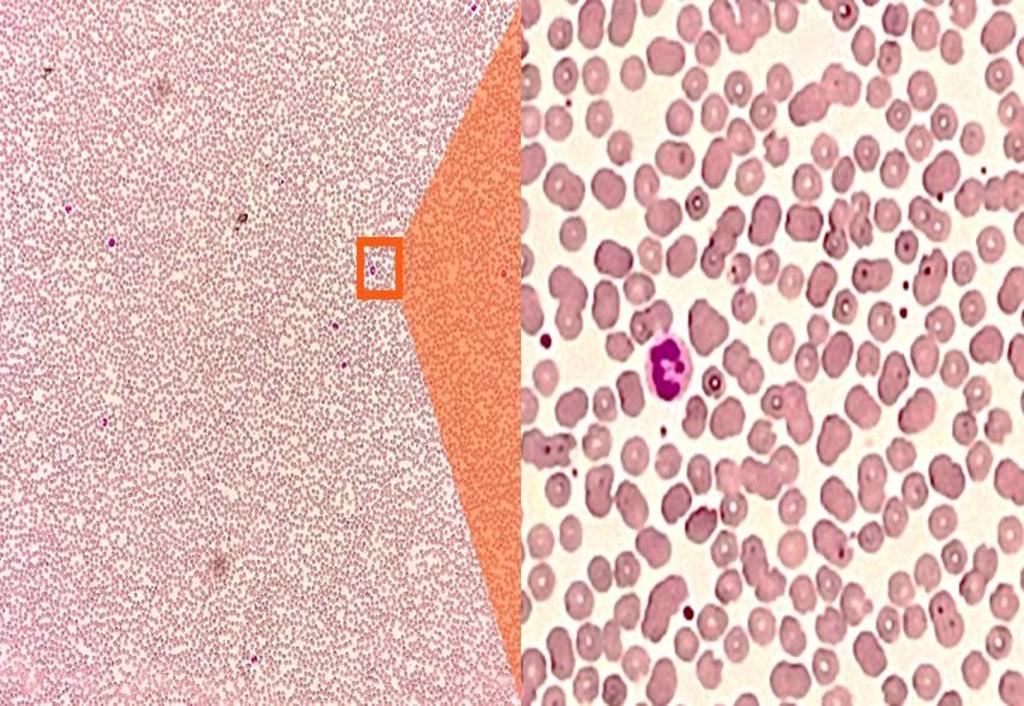

血液涂片检测示例

生物医学检测领域应用前景广阔,例如细胞病理检测、组织病理检测、真菌检测、血细胞检测、尿有形成分分析等。